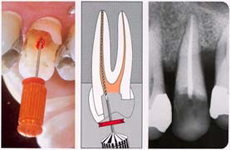

ЭНДОДОНТИЯ – ЛЕЧЕНИЕ КОРНЕВЫХ КАНАЛОВ ЗУБА

В результате кариеса или разрушения зуба бактериям открывается доступ к корневому каналу (пульпе), что ведет к воспалению, а иногда и к некрозу, которые могут распространиться и на соседние ткани. Если такой процесс уже начался, то необходимо удалить из канала воспаленую или некротичную ткань, чтобы предотвратить ослабление соседних тканей и потерю зуба. Такое лечение называется эндодонтическим (терапия каналов зуба), которое может быть проведено вручную или с помощью специальной аппаратуры.

Механическое эндодонтическое лечение подразумевает обработку каналов с помощью специального набора игл, при чем инфицированные ткани вручную удаляются из канала и обрабатываются его внутренние стенки. Сам канал необходимо тщательно очистить, расширить и дезинфицировать.

Машинное лечение производится с помощью эндо-мотора с апекс-локатором. Машина запраграммирована таким образом, что сама останавливается в верхушке корня. Такое лечение намного быстрее и современнее.

После обработки и очищения каналов, они заполняются специальной пастой и гуттаперчевыми штифтами, с помощью которых каналы герметически закрываются и дальнейшее проникновение бактерий и возникновение инфекции становится невозможным.